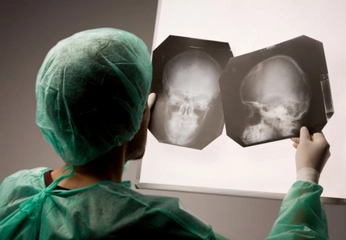

Bu durumun kesin nedenini belirlemek için bir nöroloji uzmanına veya göz doktoruna başvurmanız önemlidir. Doktorunuz, nöbetlerin ve kullanılan ilaçların göz problemlerinizle ilişkisini değerlendirebilir ve uygun tedavi veya yönlendirmeyi sağlayabilir.